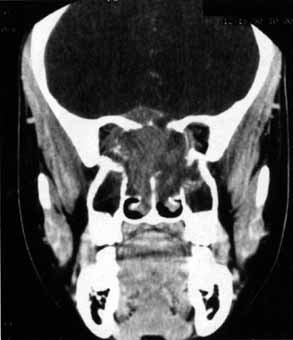

Anosmia caused by damage of cranial nerve I may be a helpful symptom of ethmoid or sphenoid sinus tumors invading the orbit (Fig. 20).44 Olfactory groove meningiomas and esthesioneuroblastomas may also present with anosmia prior to developing vision loss.45 Trauma that involves the orbit and is associated with anosmia should be considered a basilar skull fracture with potential for cerebrospinal fluid leak until proven otherwise (Fig. 21).

Fig. 20 A 13-year-old child presented with a 2-week history of sinusitis and anosmia. Her visual acuity decreased to to 20/400 1 day prior to admission. Computed tomography shows a large ethmoid tumor extending through the cribriform plate and optic canal. A rhabdomyosarcoma was diagnosed by biopsy.

Fig. 21 A 21-year-old man sustained a skull fracture from a motor vehicle accident 2 months prior to this examination. The patient describes anosmia since the accident. Computed tomography discloses a large medial wall orbital fracture extending through the cribriform plate (arrow). Orbital reconstruction was performed through a frontal craniotomy where dura was found incarcerated within the fracture. The orbital fracture was repaired by cranial bone grafting.